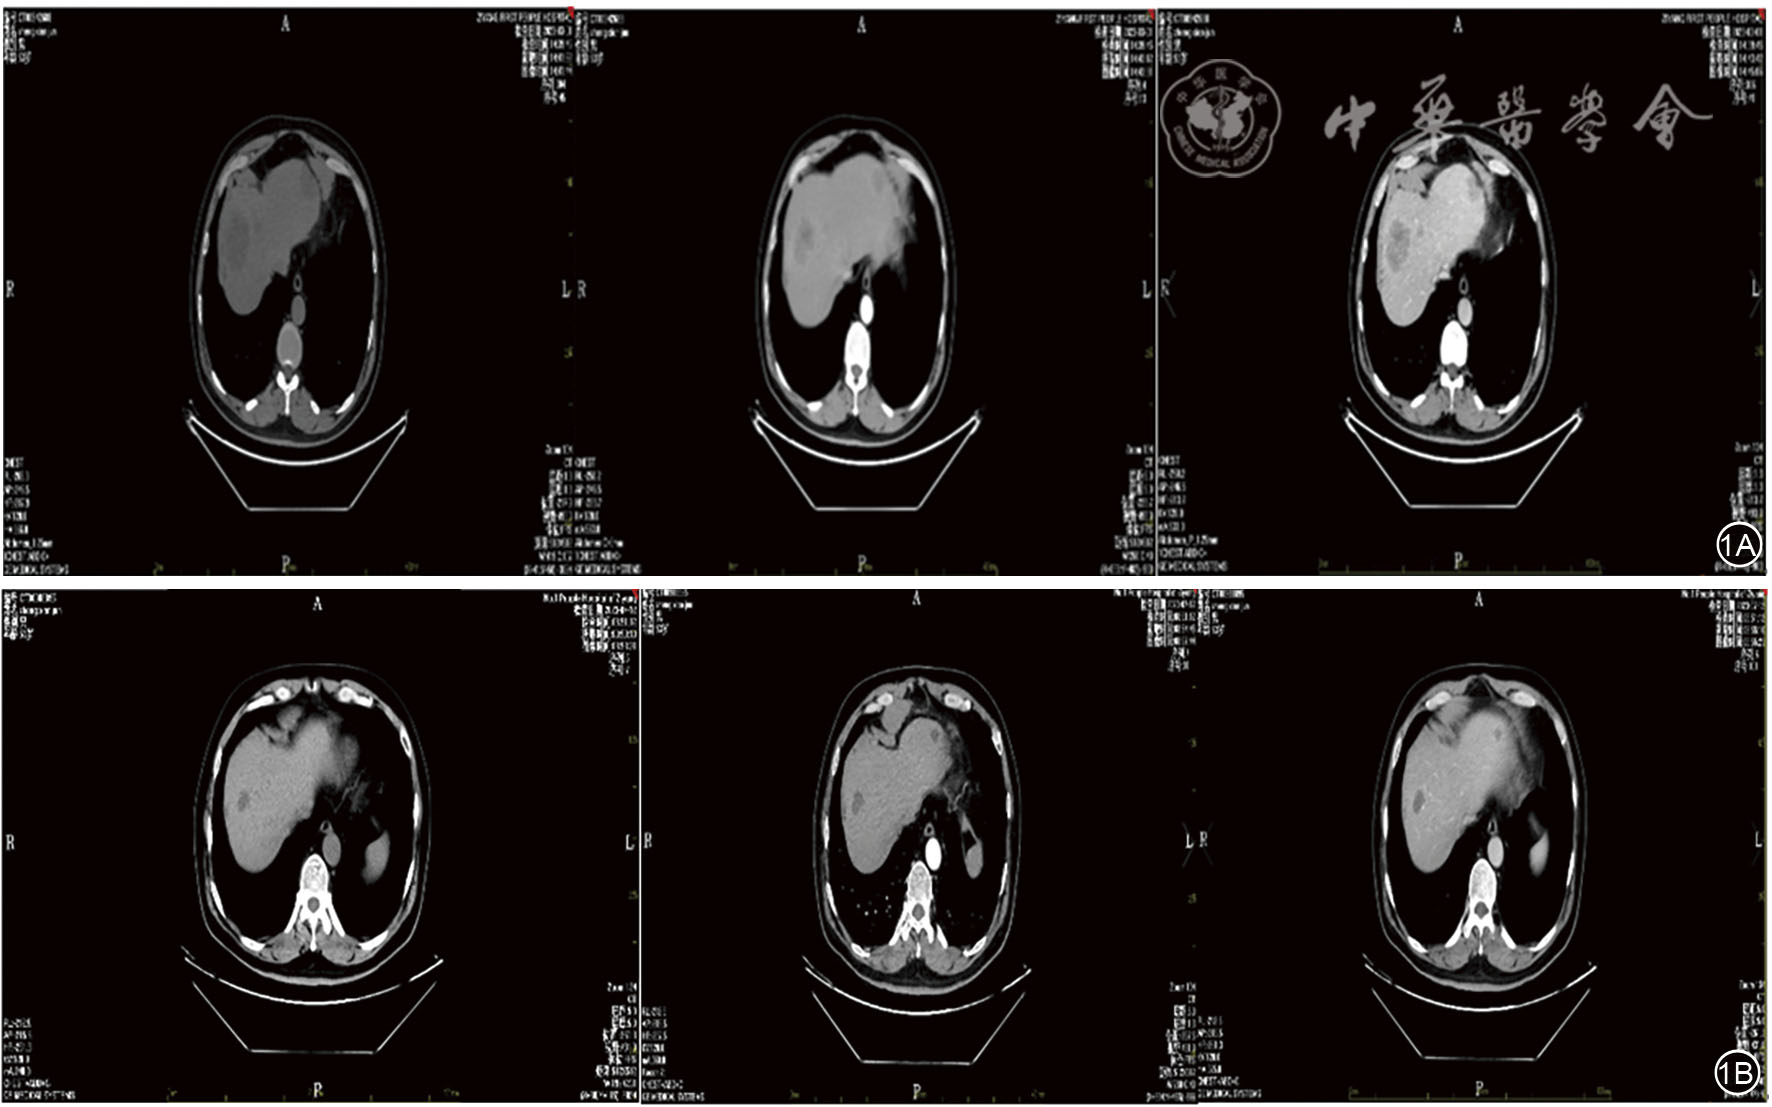

图1 试验组患者DEA-TACE治疗前后CT图。 1A: DEA-TACE治疗前;1B: DEA-TACE治疗后。DEA-TACE:载药微球-经导管肝动脉化疗栓塞术。